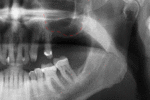

Success or failure of implants depends on the health of the person receiving it, drugs which affect the chances of osseointegration and the health of the tissues in the mouth. The amount of stress that will be put on the implant and fixture during normal function is also evaluated. Planning the position and number of implants is key to the long-term health of the prosthetic since biomechanical forces created during chewing can be significant. The position of implants is determined by the position and angle of adjacent teeth, lab simulations or by using computed tomography with CAD/CAM simulations and surgical guides called stents. The prerequisites to long-term success of osseointegrated dental implants are healthy bone and gingiva. Since both can atrophy after tooth extraction, pre-prosthetic procedures such as sinus lifts or gingival grafts are sometimes required to recreate ideal bone and gingiva.

When a more exacting plan is needed beyond clinical judgment, the dentist will make an acrylic guide (called a stent) prior to surgery which guides optimal positioning of the implant. Increasingly, dentists opt to get a CT scan of the jaws and any existing dentures, then plan the surgery on CAD/CAM software. The stent can then be made using stereolithography following computerized planning of a case from the CT scan. The use of CT scanning in complex cases also helps the surgeon identify and avoid vital structures such as the inferior alveolar nerve and the sinus.[17][18](p1199)